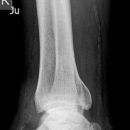

distaler Unterschenkelschaft

Maisonneuve

Spiralfraktur Tibia